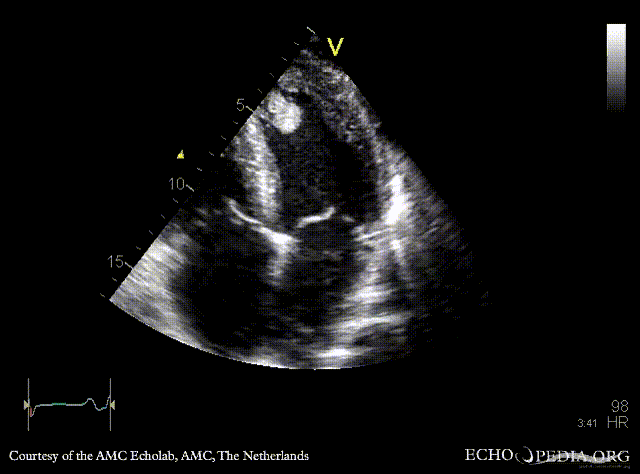

Case 142